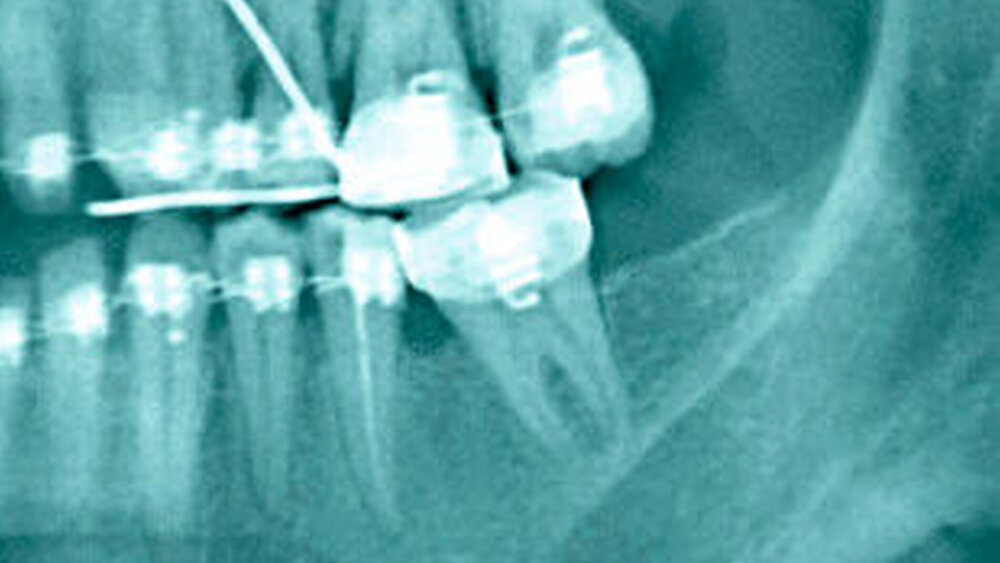

Die kieferorthopädischen Behandlungen wiesen bezüglich Schweregrad oder Behandlungsspektrum eine große Spannbreite auf: von Behandlungen einzelner Segmente (kieferorthopädische Extrusion nach Hemisektion der Zähne 46, 47 als Teil einer „Bloodless tooth extraction”) bis zu Behandlungen des gesamten Zahnbogens unter skelettaler Verankerung.

Als Nebenwirkungen wurden bei einem Teil der Patienten post-therapeutisch Wurzelresorptionen, sklerotische Knochenareale, erweiterte Parodontalspalten, und unvollständiger kieferorthopädischer Lückenschluss mit geringer Wurzelparallelität beschrieben.